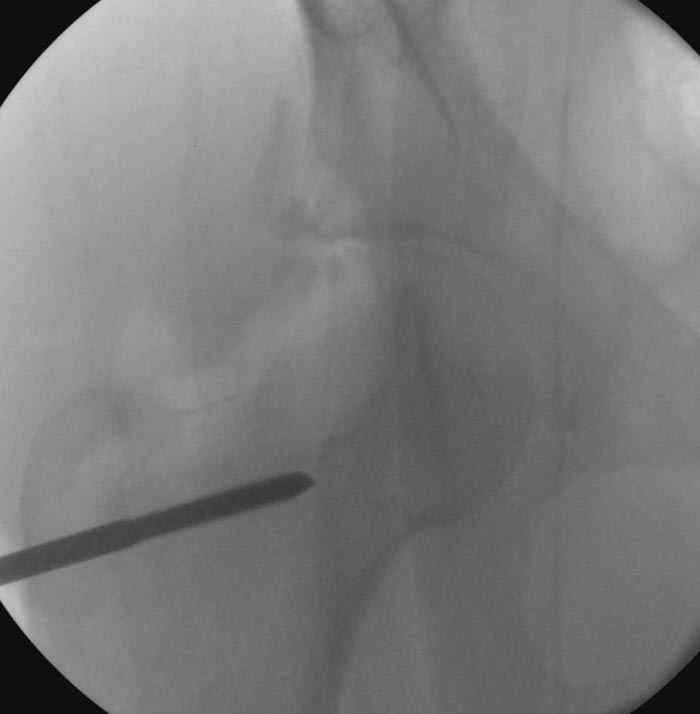

Интраоперционные N5 косая запирательная и N6 подвздошный снимок

На рисунке N1 предоперационный план лечения ложного сустава шейки бедра- линия ложного сустава, угол и направление введения импланта, клиновидная остеотомия в градусах и миллиметрах, второй снимок после коррекции, расчет, на сколько удлиняется конечность и размеры импланта;

N3 рисунок окончательный снимок, после операции моя рентгенограмма должен выглядеть примерно как эта картина. На N4 снимке клин перед удалением; N5 послеоперации 3 нед.; N6 окончательная рентгенограмма.

варус при проксимальном отделе 95 градусной пластиной.